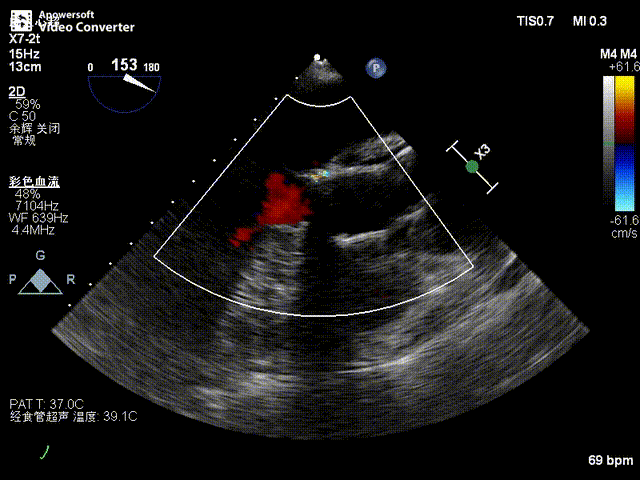

术后超声影像图

患者全麻后,于左侧心尖3-4cm处进行微创手术切口。在DSA及超声引导下,输送Ken-Valve瓣膜系统进入左心室,边调弯边推送,使得瓣膜在术中始终保持较好的同轴性,从送入输送器到瓣膜释放不足十分钟。术后即刻患者反流消失,于外科杂交手术室拔除气管插管,次日即由ICU转入普通病房。

张海波教授:此病例为单纯的主动脉瓣关闭不全患者。CT分析提示,主动脉根部角度为78°,为重度“横位心”患者,给瓣膜的植入带来了巨大的挑战。术中采用了Ken-Valve输送系统,进入左心室后进行调弯,减少了对升主动脉的影响,从而增加了瓣环上的操作空间,保证了瓣膜的同轴性,整个手术过程十分顺畅。对于重度横位心、单纯主动脉瓣关闭不全的病例,这是难能可贵的。术后即刻患者反流消失,结果令人满意。由于Ken-Valve瓣膜具有独特的定位件及裙边设计,其他长支架自展瓣难以企及。